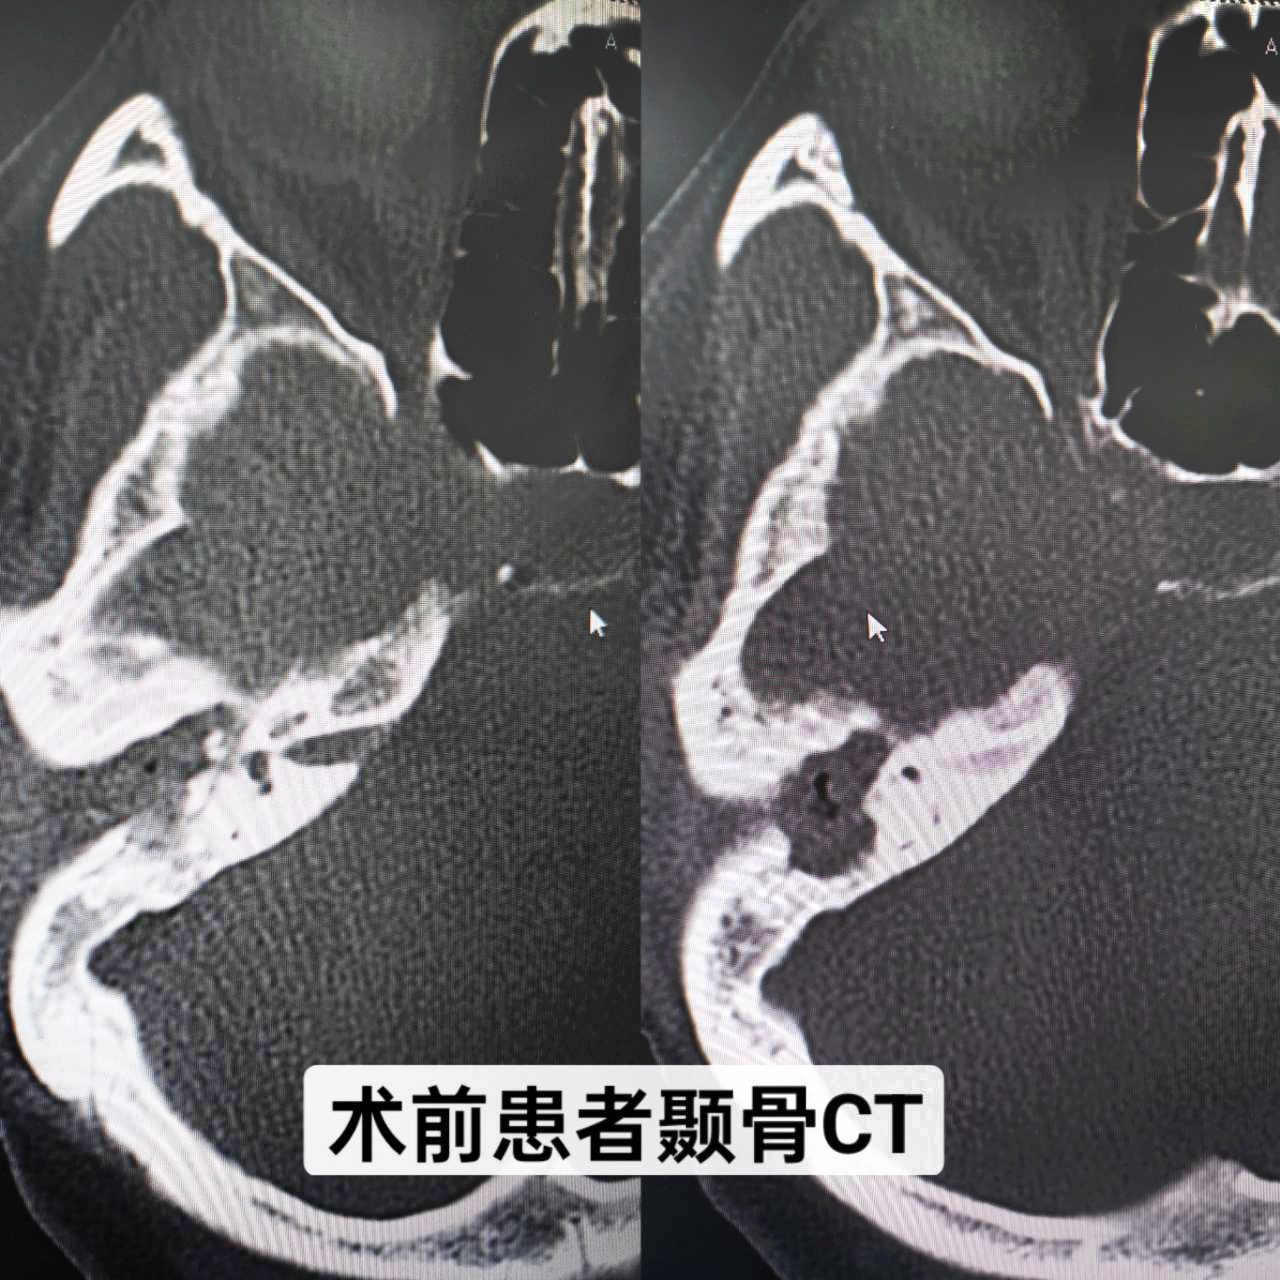

患者,女,34歲,幼兒時發(fā)生過中耳炎,經(jīng)治療后已明顯好轉(zhuǎn),但最近一個月反復(fù)右耳腫痛、流膿、流水,伴聽力下降,嚴(yán)重影響生活,來我院就診。耳內(nèi)鏡示:右耳外耳道縮窄,肉芽組織及膿血性分泌物填充,鼓膜窺不及;顳骨CT示:右側(cè)中耳鼓室擴(kuò)大,見軟組織影填充并向外耳道延伸,右側(cè)聽小骨骨質(zhì)吸收,形態(tài)小,部分聽骨欠清,考慮:右側(cè)膽脂瘤型中耳炎(累及右側(cè)外耳道)。耳鼻咽喉科副主任顏抗經(jīng)過閱片及結(jié)合患者病史,判斷患者是中耳膽脂瘤造成聽小骨斷裂,建議患者入院手術(shù)治療。